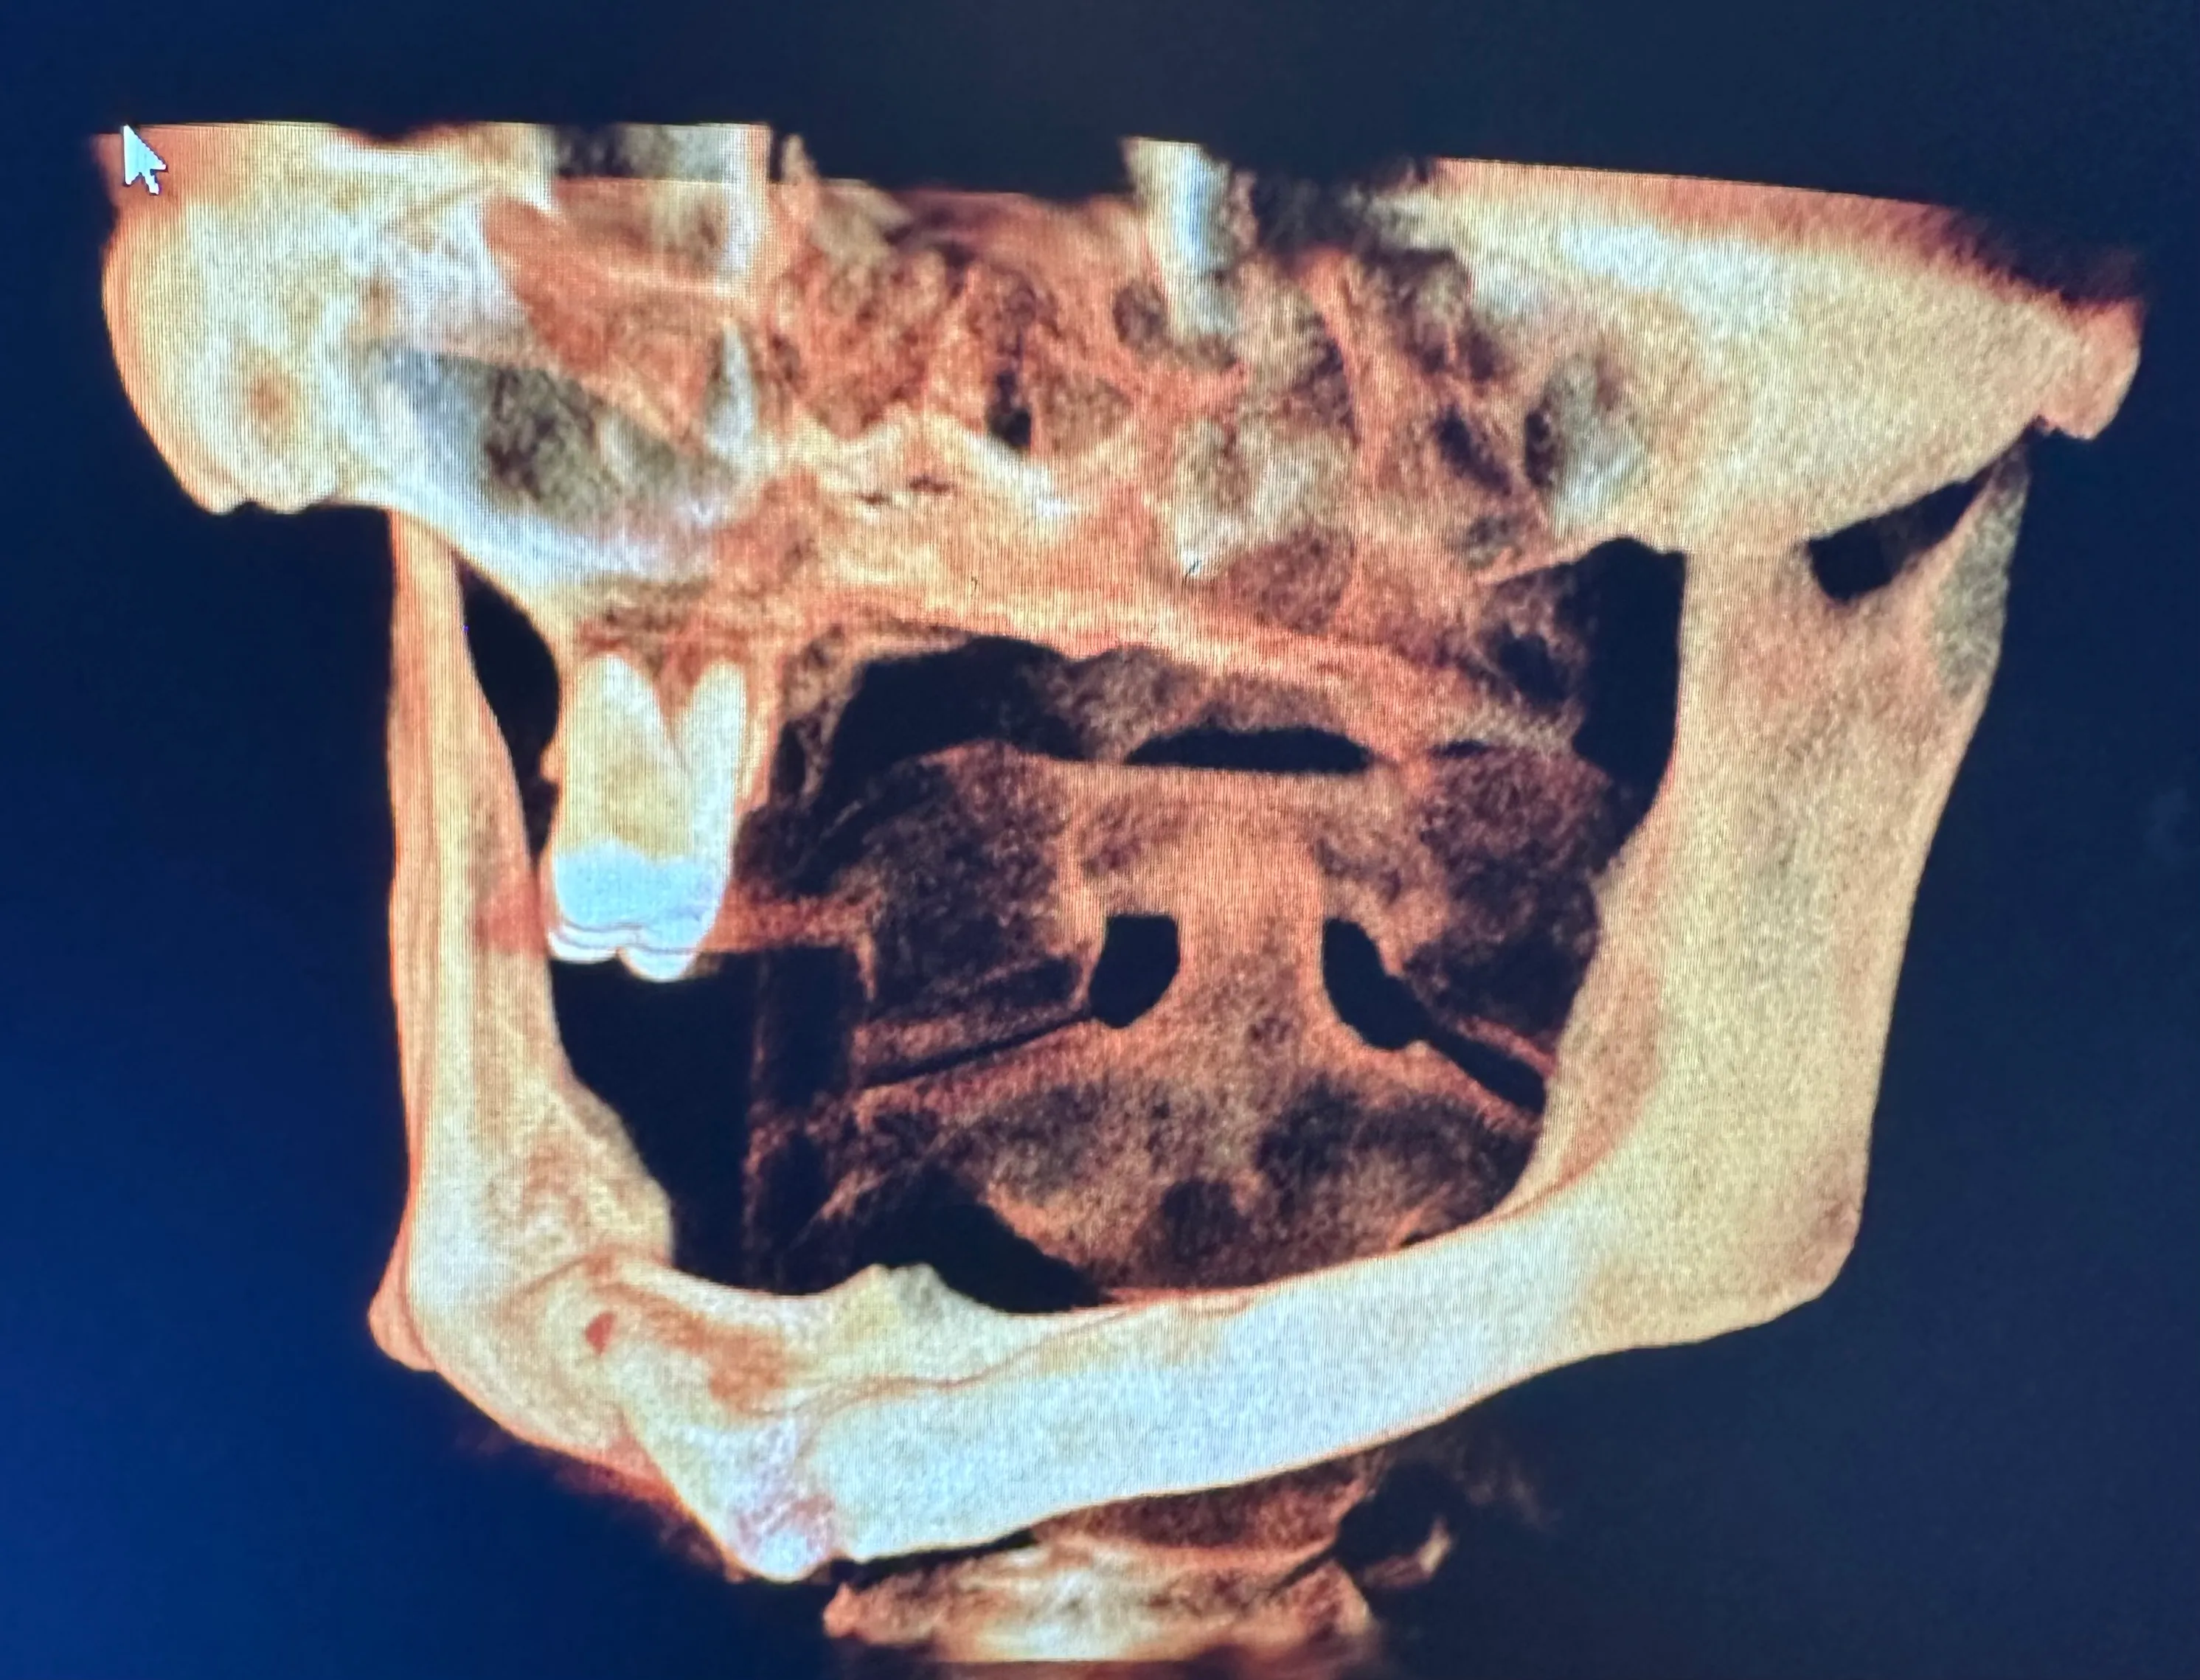

X-ray image of a jaw with dental implants and surgical plates, highlighting the alignment of teeth and orthopedic hardware.

Normally, implants are placed in the maxilla to replace missing teeth in the upper jaw. However, some patients have such severe bone loss that there isn’t enough to place an implant safely. In this case, longer implant screws can be used to reach the cheekbones, which are used as an anchor instead.

Zygomatic dental implants are sometimes called “rescue implants” because they can help patients achieve a fully functional bite and aesthetically pleasing smile when bone grafting isn’t possible.